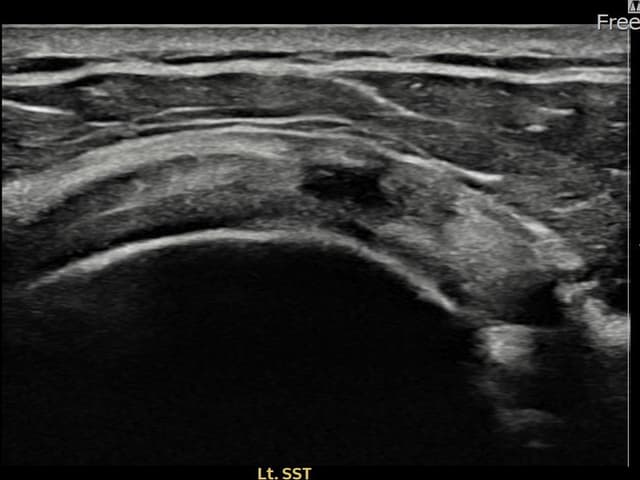

左侧 冈上肌腱 石灰化肌腱炎

9mm × 7mm